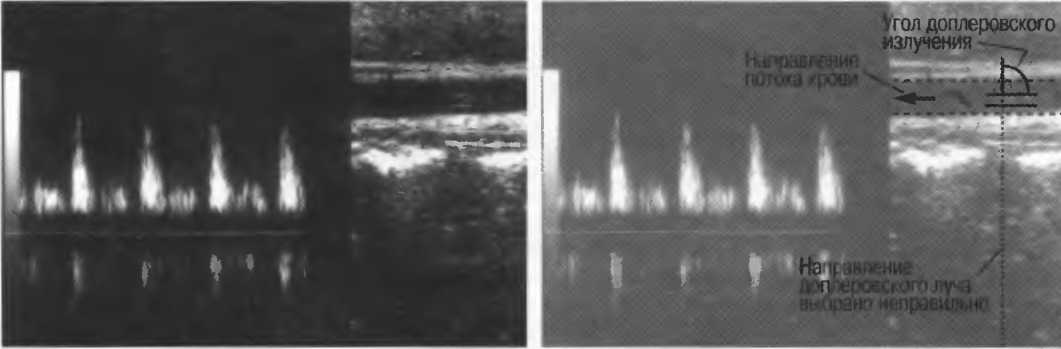

Рис.2а. Доплерографическое исследование в импульсном режиме, регистрирующее скорость кровотока чуть выше уровня бифуркации аорты.

Рис.2б. Артефакт искажения доплеровского спектра: пик скорости каждой волны расположен ниже базовой линии, определяя этим наличие потока в противоположную сторону. Этот артефакт возникает, когда частота повторения импульса недостаточна для измерения высоких скоростей движения отражающих структур.

4. Режим дуплексного доплеровского сканирования. Кровеносный сосуд изображается в В-режиме, скорость кровотока определяется доплерографически. Такое сочетание В-режима и доплерографии позволяет более точно получить информацию с данного конкретного сосуда (рис. 2в,г).

Рис.2в. Дуплексное доплеровское сканирование внутренней сонной артерии. В левой половине представлена кривая скоростей кровотока, демонстрирующая пульсирующий поток по направлению к датчику. Если бы поток был направлен от датчика, то спектр скоростей кровотока был бы направлен вниз от изолинии. Кривая скоростей носит волновой характер в соответствии с сердечным циклом. В правой половине развертки представлено изображение в В-режиме, которое показывает, откуда был снят спектр скоростей кровотока.

Рис.2г. Результаты исследования могут быть искажены, если угол сканирования выбран неправильно. Это та же общая сонная артерия, представленная на рис. 2в, однако угол сканирования составляет около 90°. В результате поток выглядит турбулентным, хотя на самом деле он совершенно нормален. В данном случае неправильно выбран угол сканирования, а с потоком все в порядке.